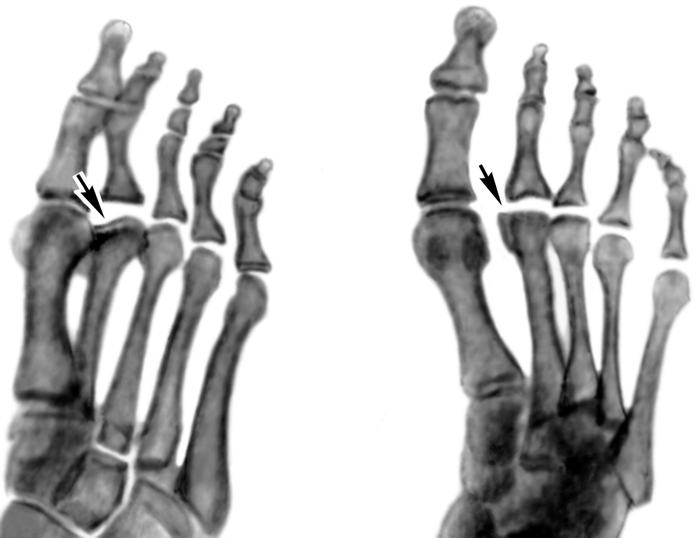

Костное ремоделирование после перелома